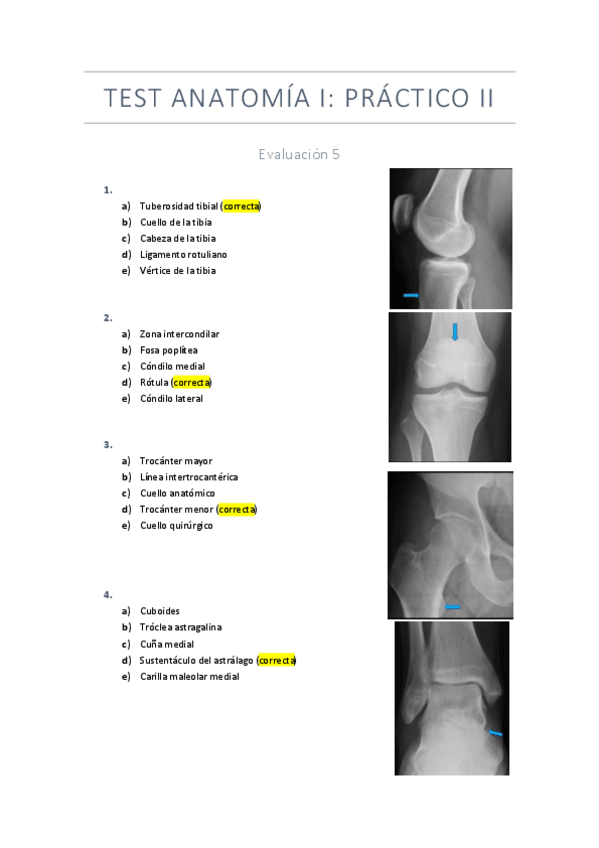

Exámenes test Anatomía I

He publicado nuevos examenes de 1º Anatomía Humana I: Exámenes test Anatomía I

Test-practica-2.pdf